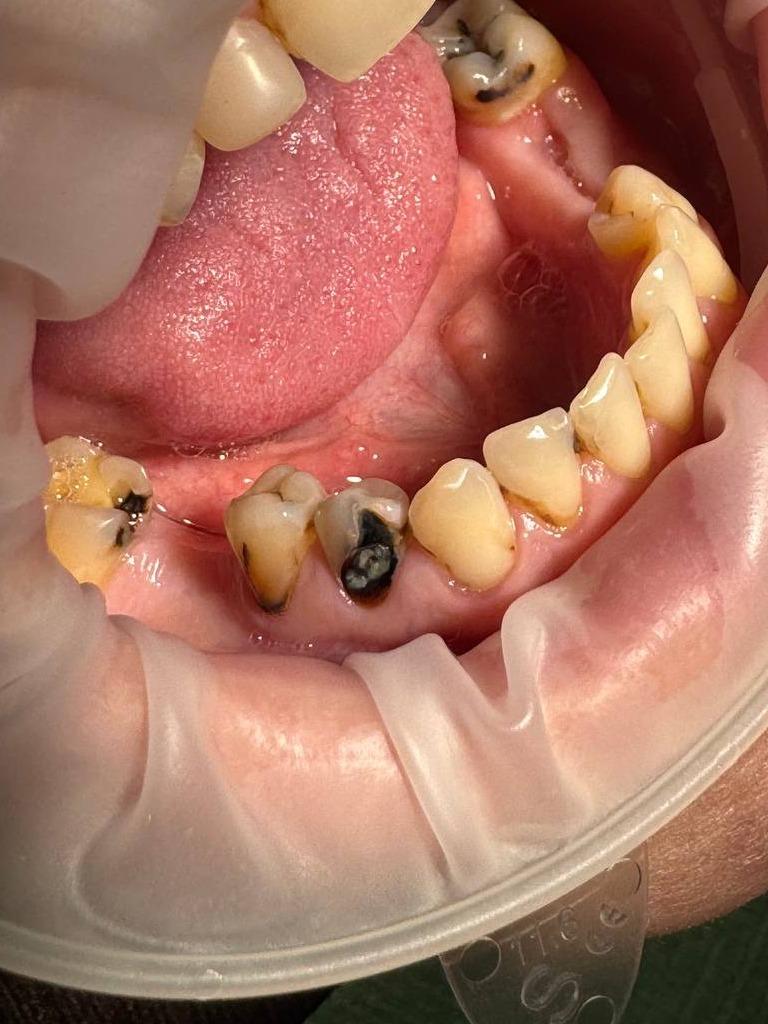

Пациент обратился с жалобами на эстетический дефект. Полная санация полости рта у пациента. Проведено лечение кариеса всей полости рта.